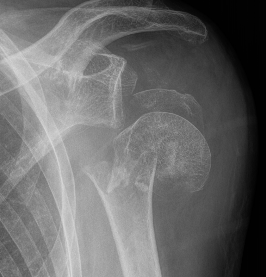

Severe comminuted proximal humerus fractures

100% displaced / off ended

Fracture - dislocations

- comminuted, 3 or 4 part

- head spltting fracture

- off ended / 100% displaced

Unreconstructable fracture - 4 part, comminuted, head spltting fracture